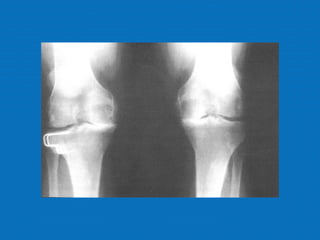

RADIOLOGIA

No início da doença não se observam anormalidades. Com seu

desenvolvimento, observam-se:

• Diminuição do espaço intra-articular

• Esclerose subcondral (eburnação)

• Osteófitos;

• Erosão e anquilose óssea (pseudocistos ósseos).

RADIOLOGIA No início dadoença não se observam anormalidades. Com seu desenvolvimento, observam-se: • Diminuição do espaço intra-articular • Esclerose subcondral (eburnação) • Osteófitos; • Erosão e anquilose óssea (pseudocistos ósseos).